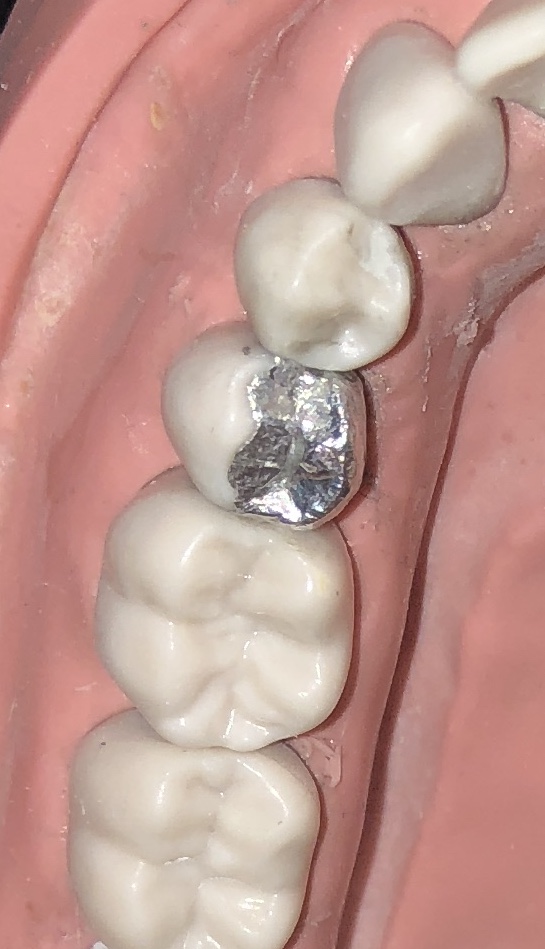

Module 5 of the Operative Dentistry course considered restoration of Endodontically treated teeth using bonded amalgam restorations. Teeth LL4 and LL7 were prepared with MODL cavities to simulate to extent of tooth tissue loss often encountered in root filled teeth. As amalgam does not bond to enamel or dentine it is important to incorporate appropriate resistance and retention form in cavity design. Grooves and amalgapin preparations were incorporated into the dentine of LL4 and a nayar core was planned in the LL7 to utilised the pulp space and coronal portion of the root canal system for retention. The cavities were isolated with an annealed automatrix which was adaptation marginally and secured with wedges from the lingual surface. The enamel and dentine were etched and bonded and panavia V5 applies to base of the cavities. Tytin amalgam was packed and carved with fissure pattern and cusp shapes incorporated. The automatrix was removed and final fissure and cusp carving performed with burnishing and the use of green and brown stones to polish. A bristle brush was useful to achieve a final high polish. Equally the restoration could be sandblasted if a matte finish was preferred. An indirect restoration may be later considered particulary in root filled teeth where protection from fracture is considered appropriate. Although composite rsi restoration may offer a more aesthetic and preferred option to restore with – especially with future phase down of amalgam use planned – amlagam is still a very useful material in scenarios where moisture control is suboptimal and continues to provide predicable and robust outcomes backed up with long term success rates.